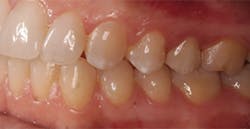

The next day, a good case opportunity presented itself. I had to prepare and scan No. 13 for a crown. I figured it was anteriorly positioned enough that I could test the esthetics, but it was posterior enough that the stakes weren’t too high. Nevertheless, you can see from Figures 1a–1c that we were thrilled with the results. Additional restoration examples can be seen in Figures 2 and 3.

Figures 1a–1c:

1a: Prepared No. 13, 1b: True Definition scan merged with clinical photo, 1c: No. 13 with Lava Esthetic full contour zirconia crown